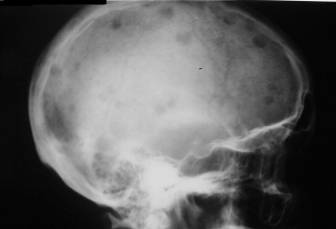

MIELOMUL MULTIPLU

Aspectul radiologic

La nivelul craniului se evidentiaza zone de osteoliza rodunde de dimensiuni variabile în jur de 10mm cu contur net aratând ca niste gauri facute cu burghiul.

La nivelul coastelor apar numeroase

zone de osteoliza, coastele sunt îngrosate, corticala este

subtiata sau distrusa si pot aparea multiple fracturi.

Prezenta fracturilor costale numeroase în afara unui traumatism major

cunoscut pledeaza pentru mielom.

La nivelul coloanei vertebrale, leziunile intereseaza la început una sau mai multe vertebre izolate care prezinta o intensa decalcificare apoi aparând zone de osteoliza. Corpii vertebrali se prabusesc, iau aspect cuneiform, se produc fracturi si cifoze.